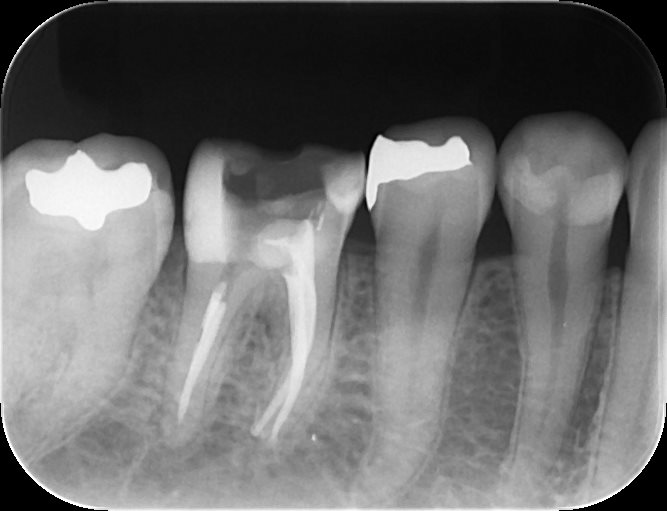

根管治療は必ずラバーダムを使用しております。

根管治療後のデンタルX戦写真

来院回数は、根管治療で3回、セラミック治療で2回で終了です。